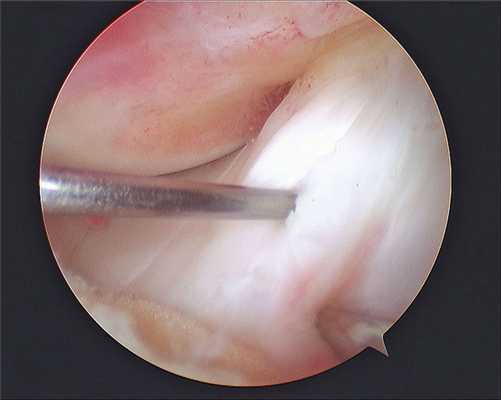

В проекции суставной щели (коленного, плечевого, голеностопного, локтевого, других суставов) делают два-три маленьких разреза-прокола (порта). В один из них вводят тонкий оптический прибор - артроскоп, диаметром 2-4 мм, длиной 12-14 см, который соединен с цифровой видеокамерой. Через другой порт вводят специальный щуп или тонкие инструменты.

Ход операции хирург контролирует, глядя в монитор, где имеется увеличение изображения в 30 - 50 раз по сравнению с реальными размерами всех внутрисуставных структур. Такая методика обеспечивает высочайшую точность манипуляций в суставе и исключительную аккуратность манипуляций.

Изображение полости сустава.

В целях высокоинформативной диагностики специалист через микропортал вводит рабочую трубку устройства внутрь сустава, в которую вмонтированы система ультрасильных линз, мощный световой источник и видеозаписывающая цифровая техника. Все структуры, что «видит» артроскоп, визуализируются на экране в «живом» виде, причем изображение поступает в многократно увеличенном формате. Врач может найти точное расположение травмы или дегенеративных изменений, установить характер патологии, степень тяжести и принять меры.

Видео в реальном времени транслируется на экране, выявляет любые существующие дефекты в больном сочленении. Если врач посчитает нужным выполнить регенерацию патологических элементов, он создаст дополнительный разрез (6-8 мм), через который нужным инструментом из микрохирургического набора устранит обнаруженный дефект. Он может сделать частичную резекцию костно-хрящевых тканей, пластику связок и сухожилий, сшивание или удаление (частичное, полное) мениска, экспроприировать хондромные тела, извлечь выпот и гной, ввести противовоспалительные лекарства, взять фрагмент тканей или синовии для изучения их состава и др.